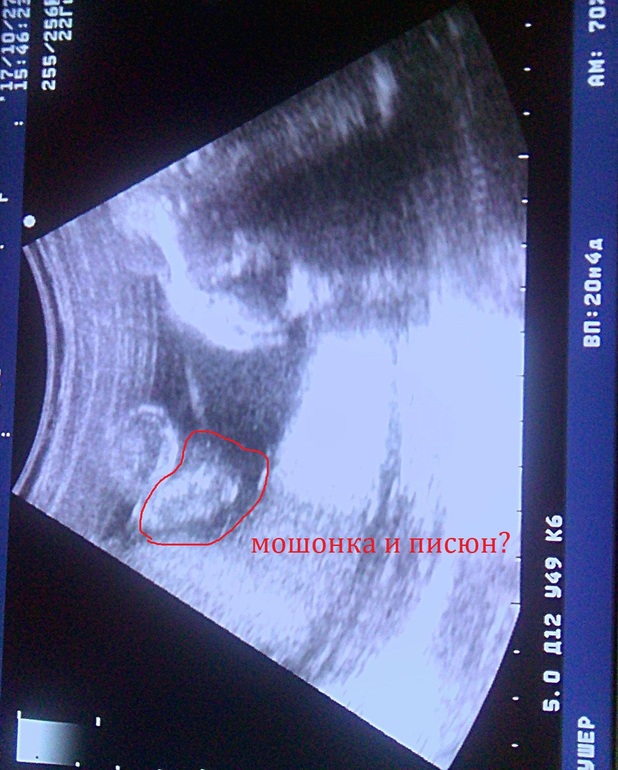

Дарья Бартенева 8 лет Девочки помогите понять по фото, это мужские половые органы? Посмотрите еще 20 записей на эту тему Отменить Ответить Татьяна на узи какая часть ножки или что?срок то большой понятно весь малыш не поместится))))))) 15.11.2017 Ответить Татьяна честно фото не четкое не понятно.....а узист пол не сказал? 15.11.2017 Ответить Дарья Бартенева 15.11.2017 Ответить Ленусик вообще не понятно где что, все размыто ... узист то что сказал? с какой стороны фото вообще ребенок то?) 15.11.2017 Ответить Чаты Беременных Выберите чат: Январята-2026 Февралята-2026 Мартята-2026 Апрелята-2026 Майчата-2026 Июнята-2026 Июлята-2026 Августята-2026